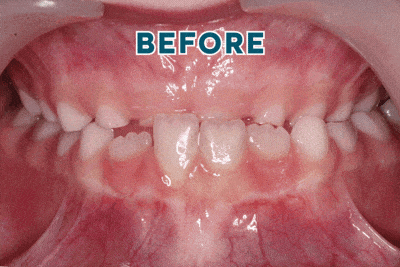

Case Study: Early Underbite Treatment in Kids

Avoid Extensive Treatment Later in Life

Early orthodontic evaluations can play an important role in identifying and addressing developing bite concerns in children. In this case, a young patient was first monitored at age 7 and began treatment at age 8 to correct a developing underbite. By guiding jaw growth at the right stage of development, early intervention helped correct the bite and reduce the likelihood of more complex treatment later.